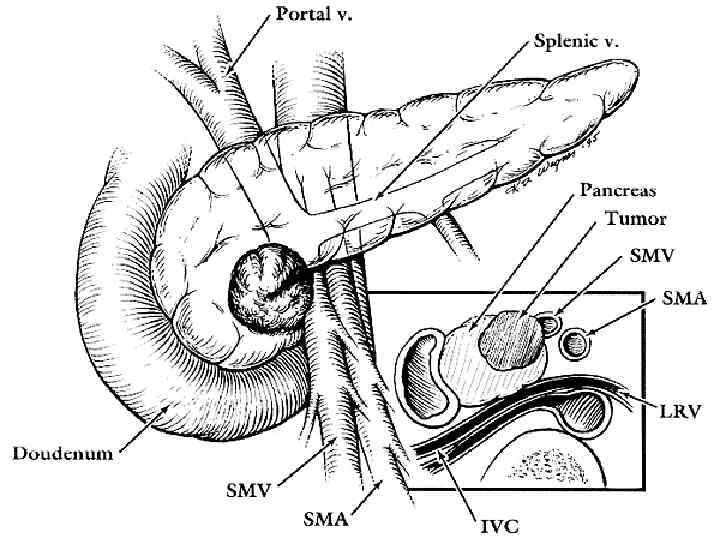

Этапы стандартной ГПДР • • • 1. Мобилизация 12 -перстной кишки 2. Выделение трубчатых структур гепато-дуоденальной связки 3. Выделение верхней брыжеечной вены 4. Мобилизация и отсечение дистальной части холедоха 5. Мобилизация и пересечение начальной части тощей кишки 6. Пересечение гепатикохоледоха после мобилизации желчного пузыря • 7. Пересечение поджелудочной железы по перешейку • 8. Пересечение связок крючковидного отростка, удаление комплекса • 9. Реконструктивный этап

Классификация вовлечения магистральных сосудов по Nakao et al в зависимости ангиографической картины и сравнение с данными послеоперационного гистологического исследования Ангиографические типы Гистологическое подтверждение вовлечения сосудов (%) Тип А – не измененная ангиограмма 0 Тип В – одностороннее сужение 20 Тип С – двухстороннее сужение 70 Тип D – стеноз, обструкция с наличием коллатеральных вен 92

Распространенность протокового рака головки ПЖ в момент «радикальной» операции 1. 2. 3. 4. 5. 6. 7. Инвазия передней капсулы ПЖ – 80% Инвазия края резекции ПЖ – 40% Ретроперитонеальная внеорганная инвазия – 80% Инвазия крупных сосудов – 60% Метастазы в регионарные лимфоузлы – 100% Метастазы в юкстарегионарные лимфоузлы – 80% Метастазы в печень – 20%

Инвазия чревного ствола и общей печеночной артерии

Резекция чревного ствола и общей печёночной артерии при выполнении ДСРПЖ Вид резекции Циркулярная резекция чревного ствола Всего Число больных с пластикой 4 без пластики 11 15

Верхняя мезентерикография после резекции чревного ствола с ушиванием обоих концов сосуда наглухо. Кровоснабжение печени осуществляется через гастродуоденальную артерию